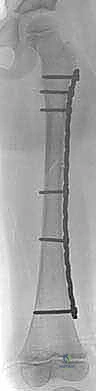

Submuscular Bridge Plating of Pediatric Femoral Shaft Fractures: An Intraoperative Masterclass

Clinical & Radiographic Imaging Archive